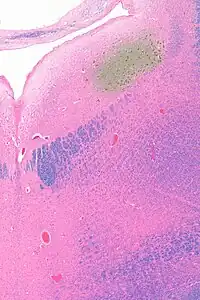

Micrograph showing the locus coeruleus. HE-LFB stain.

Micrograph showing the locus coeruleus (upper-right of image) in an axial section of the pons. The fourth ventricle (quasi-triangular white area) is in the upper-left of the image. The midline is seen on the left. The large white area in the upper-left corner is where the cerebellum would be. HE-LFB stain.